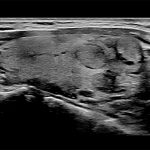

Imagini clinice:

Aplicatii: